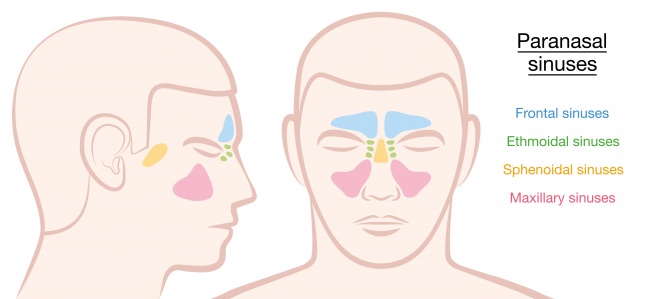

2. Paranasal sinuses

No one knows why we retain these troublesome mucus-lined cavities, except perhaps to make the head lighter.